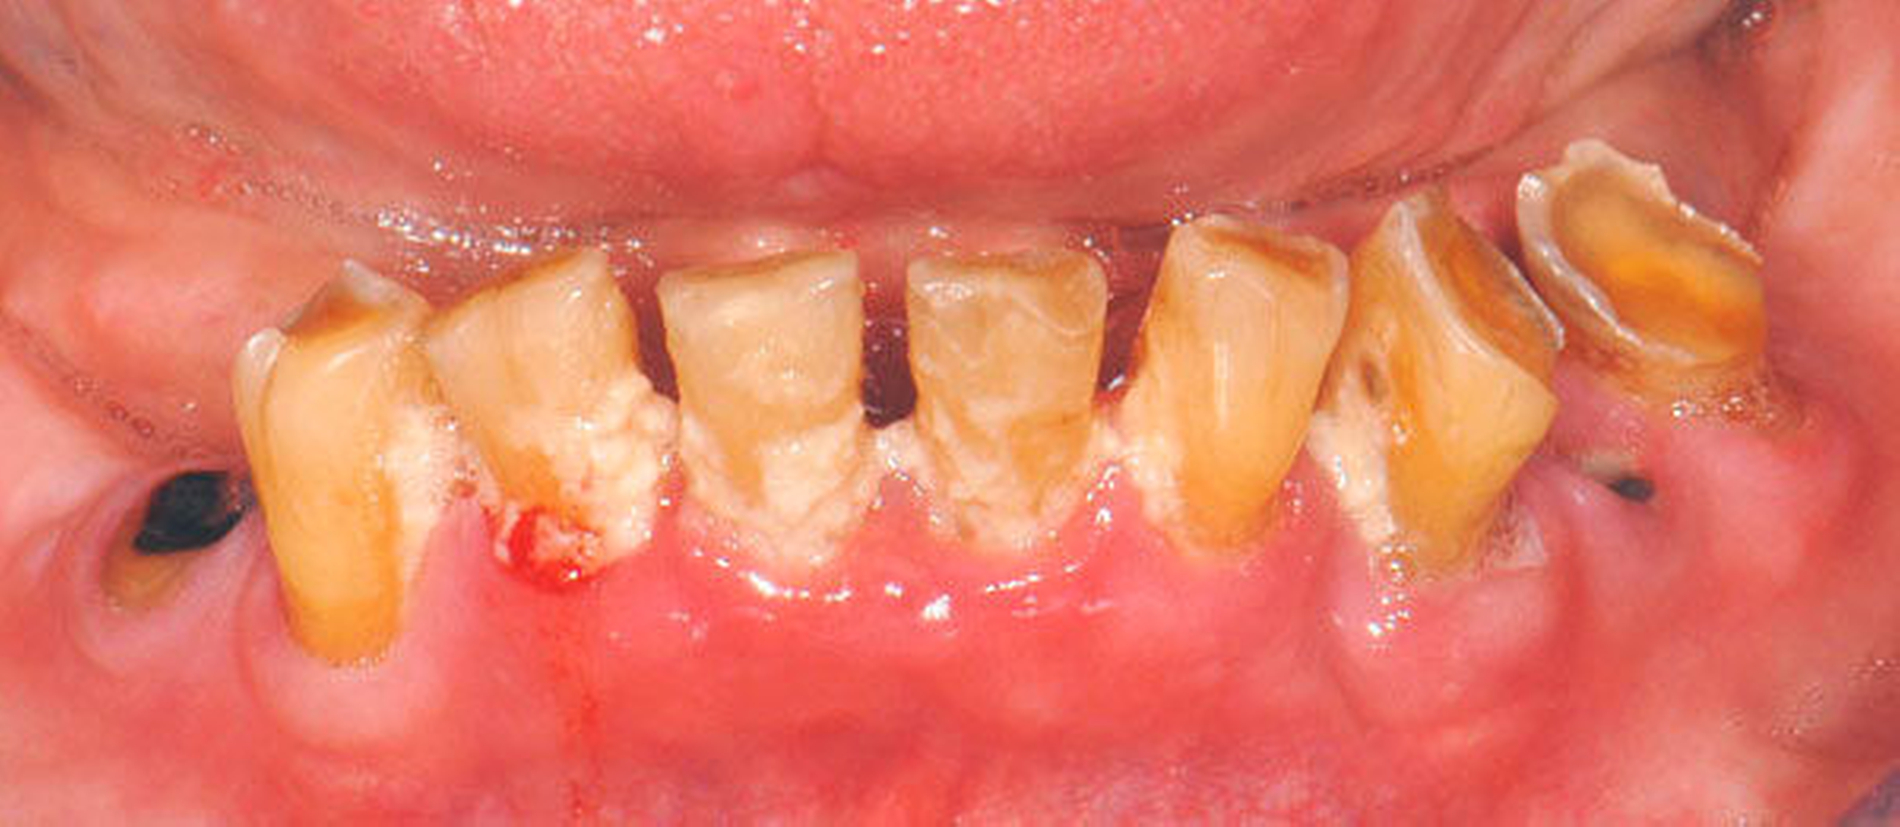

Bei älteren Patienten mit (infolge geistiger Einschränkung) vernachlässigter Mundhygiene, exemplarisch in Abbildung 5 dargestellt, wird zuweilen eine Extraktion sämtlicher Zähne vorgenommen. Eine anschließende prothetische Versorgung ist in solchen Fällen wegen mangelnder Adaptationsfähigkeit oftmals nicht mehr möglich. Dies hat zur Konsequenz, dass die Betroffenen in ihrem Aussehen, ihrer Sprachfunktion und ihrer Fähigkeit zur Nahrungsaufnahme noch eingeschränkter sind als vorher, verbunden mit vielerlei Nachteilen im psycho-sozialen Umfeld.

Wenn irgend möglich, sollte deshalb erwogen werden, einen Erhaltungsversuch wenigstens bei den gut zugänglichen Schneide- und Eckzähnen vorzunehmen, auch wenn die Prognose unsicher ist und Rezidive der Wurzelkaries zu erwarten sind. Die in Abbildung 5 gezeigte Patientin lebte zunächst noch zu Hause und wurde von einer Pflegeperson täglich betreut. Nach Umzug in ein Pflegeheim wird sie von ihrer ehemaligen Pflegerin nach wie vor ein- bis zweimal wöchentlich aufgesucht. Die Pflegerin nimmt bei ihr ein- bis zweimal wöchentlich eine Zahnreinigung mittels Zahnbürste und Interdentalraumbürsten vor, was mit einem Zeitaufwand von jeweils maximal fünf bis zehn Minuten verbunden ist. Obwohl sich nach zwei Jahren an einigen Zähnen ein Kariesrezidiv eingestellt hat, konnte der Zahnbestand gehalten werden.

Abbildung 4: Anliegen eines 76,5-jährigen Patienten (Anfrage per E-Mail). Zitat: „Mich plagt eine … Entzündung des Mundraums, die auch das Zahnfleisch meiner Zahnstummel angreift, weshalb ich nur noch Breiartiges zu essen vermag. Ein Angsthase wie ich geht zum Zahnarzt NUR unter dem Eindruck akuter Schmerzen!“

Damit wird die Hygienefähigkeit zumindest partiell verbessert und Spielraum für künftige Planungen und Vorgehensweisen unter besseren Bedingungen belassen. Das Procedere ist in den Abbildungen 4 und 5 beschrieben. Bei dem in Abbildung 4 vorgestellten Patienten lag eine Oralphobie im Seniorenalter vor. Die Verlaufsbeschreibung macht deutlich, dass selbst im fortgeschrittenen Alter eine Adaptation an zahnärztliche Interventionen im Einzelfall noch möglich ist.